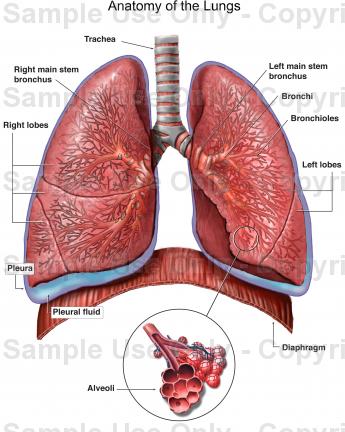

TOPIC: THE RESPIRATORY SYSTEM (HUMAN)

PARTS OF THE HUMAN RESPIRATORY SYSTEM

The human respiratory system consists of a number of organs which work together to ensure the supply of oxygen to the body cells and the removal of carbon (IV) oxide from the cells.

These organs are:

(1 ) nostrils (2) larynx (3) pharynx (4) trachea (wind pipe) (5) bronchi (6) lungs (7 ) bronchioles (8) alveoli (9) mouth

(1) Nostrils:

Air enters the body through the nostrils which are lined with a membrane of cells that secrets mucus which moistens the air we breathe.

(2) Pharynx:

The nostrils lead into the pharynx which is the lower end of the mouth cavity.

(3) Larynx:

The pharynx leads into the larynx which is also called the voice box. The larynx leads into the trachea, which is also called the wind pipe.

(4) Bronchi:

The trachea leads into the bronchi, each bronchus leads into a lung.

(5) Lungs: each bronchus leads into a lung. Inside the lungs are tiny tubes called bronchioles. The bronchioles branch again into alveoli.

TOPIC: THE RESPIRATORY SYSTEM (HUMAN)

PARTS OF THE HUMAN RESPIRATORY SYSTEM

The human respiratory system consists of a number of organs which work together to ensure the supply of oxygen to the body cells and the removal of carbon (IV) oxide from the cells.

These organs are:

(1 ) nostrils (2) larynx (3) pharynx (4) trachea (wind pipe) (5) bronchi (6) lungs (7 ) bronchioles (8) alveoli (9) mouth

(1) Nostrils:

Air enters the body through the nostrils which are lined with a membrane of cells that secrets mucus which moistens the air we breathe.

(2) Pharynx:

The nostrils lead into the pharynx which is the lower end of the mouth cavity.

(3) Larynx:

The pharynx leads into the larynx which is also called the voice box. The larynx leads into the trachea, which is also called the wind pipe.

(4) Bronchi:

The trachea leads into the bronchi, each bronchus leads into a lung.

(5) Lungs: each bronchus leads into a lung. Inside the lungs are tiny tubes called bronchioles. The bronchioles branch again into alveoli.